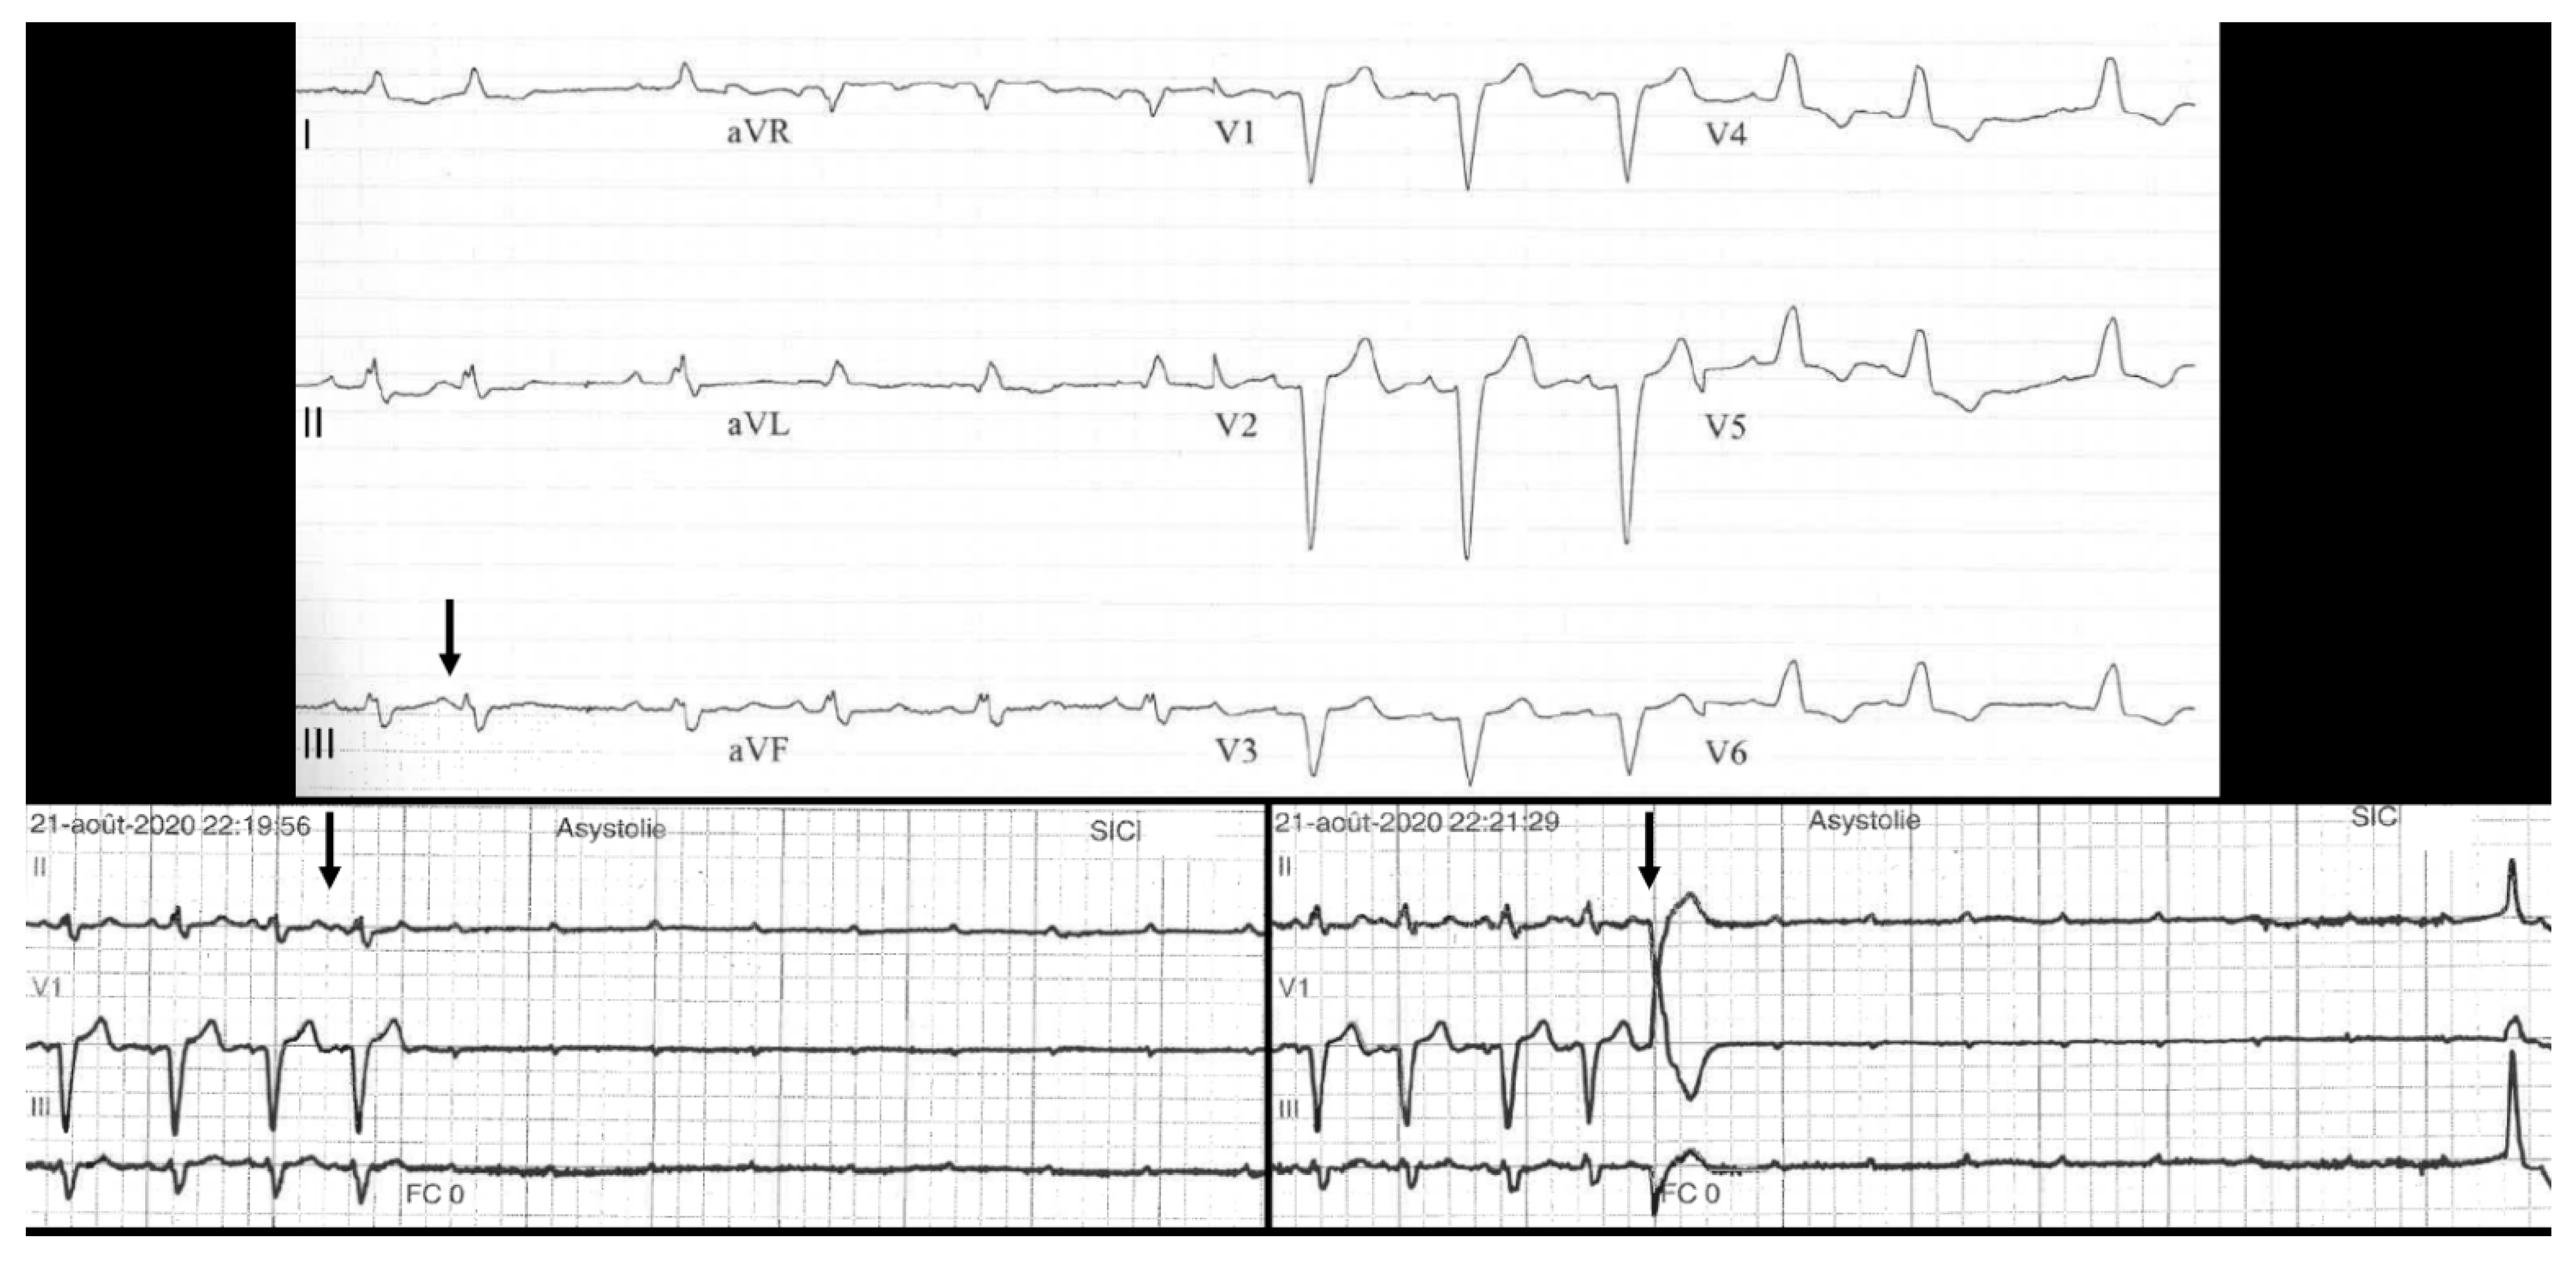

- “Intrinsic” AVB (suggesting AV conduction disease), which may be divided into four categories: Congenital heart block; tachycardia-dependent AVB; PD-AVB; and finally other acquired AVB when the preceding features/conditions are lacking (non-PD-AVB group in our study) as shown in Figure 6. Progressive cardiac conduction disease may be integrated into this last category, and refers to primary genetic degenerative diseases of genetic origin (several mutations have been described, such as in SCN5A of the cardiac sodium channel) [9]. Combined AVB initiation circumstances may be encountered in this “intrinsic” AVB group.